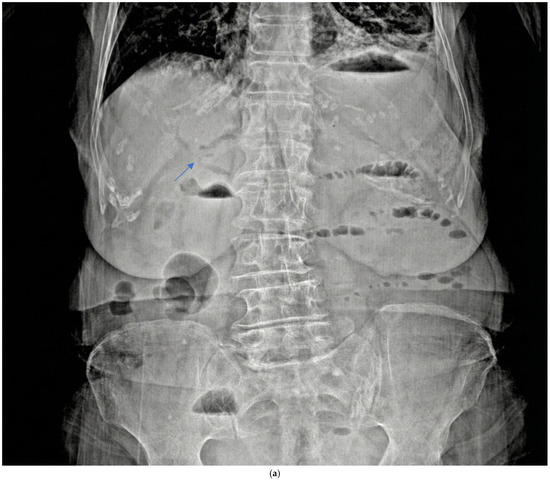

Embryo Sign on Abdominal CT as the Footprint of Cecal Volvulus: Improved Practice Through Lessons Learned from a Case Report

Cecal volvulus is a rare cause of acute abdominal pain, resulting from torsion of the cecum and ascending colon due to abnormal mobility caused by inadequate peritoneal fixation. Clinical presentation is often vague and nonspecific, which can delay diagnosis and treatment. Computed tomography [...] Read more.

Cecal volvulus is a rare cause of acute abdominal pain, resulting from torsion of the cecum and ascending colon due to abnormal mobility caused by inadequate peritoneal fixation. Clinical presentation is often vague and nonspecific, which can delay diagnosis and treatment. Computed tomography (CT) is the imaging modality of choice, as it not only confirms the presence and location of the volvulus but also identifies serious complications such as ischemia or perforation. Abdominal radiographs may be inconclusive, especially when the twisted bowel loop is fluid-filled, aligned antero-posteriorly, or obscured by adjacent gas-filled loops. We present the case of a 65-year-old woman who arrived at the emergency department with sudden-onset abdominal pain. Abdominal CT revealed classic signs of cecal volvulus, including the rarely reported ‘embryo sign,’ which proved crucial for swift diagnosis and intervention. Recognizing both common and less common CT features, such as the embryo sign, is paramount for rapid diagnosis and appropriate management in emergency situations. Familiarity with the full radiologic spectrum of this condition can significantly improve patient outcomes. Full article